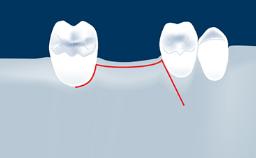

- intraoperative complications of lateral window sinus floor elevation

- intraoperative complications of transcrestal sinus floor elevation